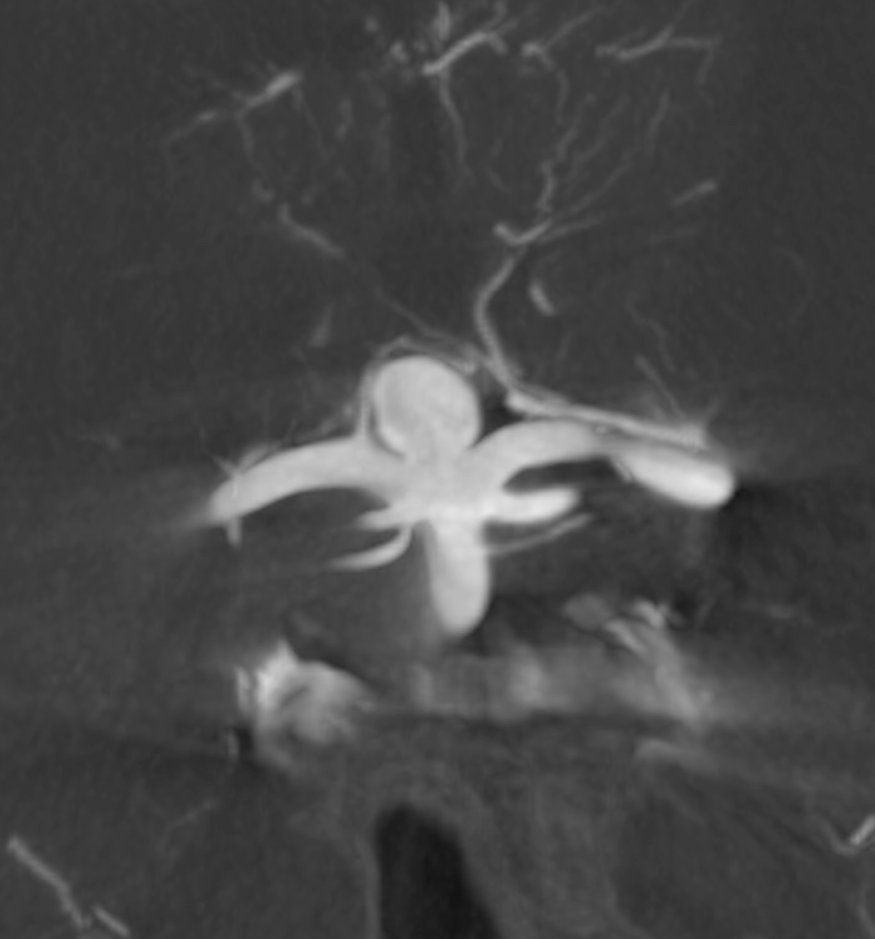

Basilar Bifurcation

Basilar tip aneurysm. A Percheron artery originating from right P1 is already evident.

3D (5 seconds) acquisition. In this case, all 3D and Vaso-CT acquisitions have been made with manual bilateral vertebral artery injection.

Below is Vaso-CT before Artisse. 22 cm FOV, 20 second acquisition. Bilateral pure contrast (300 mg/ml)Â manual injection with 20 ml syringes. Thin MIP reconstruction. No further reconstruction. The Percheron artery is well recognizable.

2 mm MIPs reconstructions